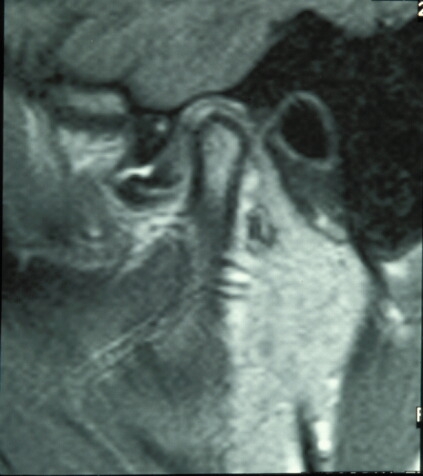

Untreated, clicking may, but not always, progress to locking, in which the disk becomes so abnormally shaped and displaced that it effectively acts like a door-stop, preventing the mandibular condyle from undertaking a full range of movements. This results in ‘locking’ of the jaw which may occur on either opening or closing of the mouth (open lock, closed lock; see Figure 2).